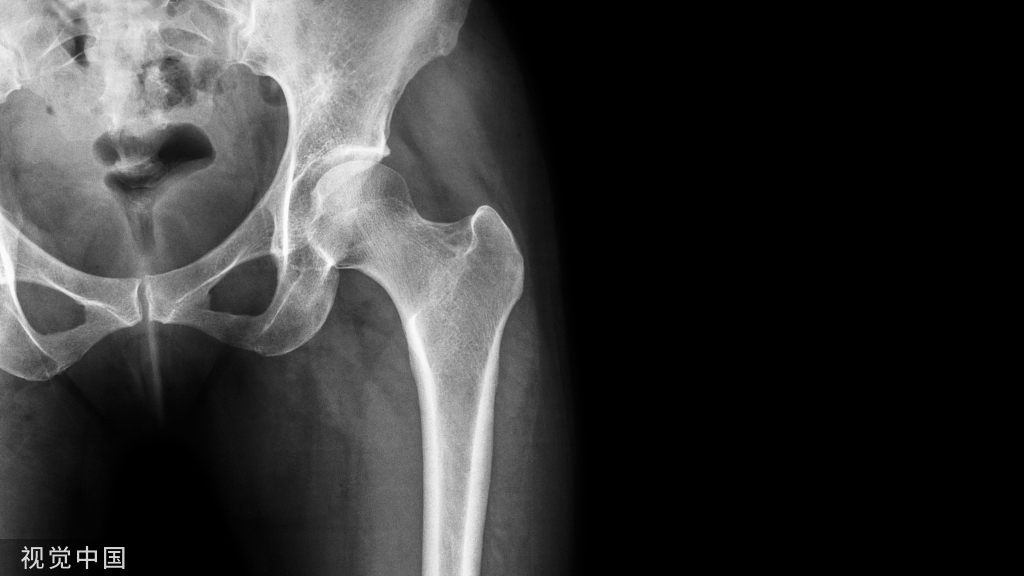

髋关节穿刺:

1.在髂前上棘与耻骨结节连线的中点,腹股沟韧带下2cm,股动脉的外侧垂直进人

2.在大转子下缘的前面,与肢体长轴呈45°角向上向内进针。推进时应使针贴近股骨转子间线,约进人5~10cm可进入关节腔

3.在大转子中点与髂后下棘连线的中外1/3处垂直进针

常用的途径

侧方穿刺途径:自大粗隆的最下方沿股骨颈方向的内上方刺入关节腔。

前方穿刺途径:自腹股沟韧带的中点向下、向外各2.5cm处,即沿股动脉鞘向外侧垂直刺入。